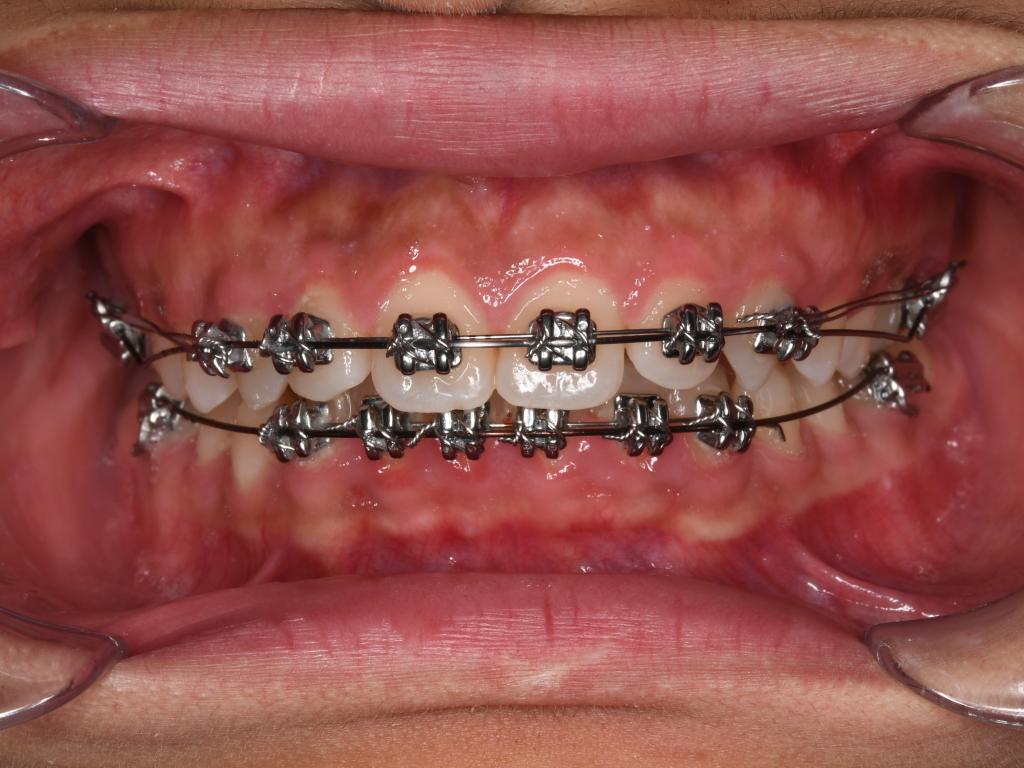

二、固定矫治器

疫情期间注意事项:

(1) 挂牵引橡皮筋的患者,每次取戴橡皮筋时做好手卫生(勤洗手)。

(2) 做好口腔清洁,保持牙齿与矫治器的清洁卫生。

(3) 进食时注意避免啃咬坚硬食物,减少矫治器损坏与脱落。

(4) 因为疫情短期无法复诊:为了大家的安全考虑,可延期就诊,偶尔的复诊延期,不影响矫治效果。必要时与主治医生取得联系,拍摄口内照片图文咨询。

紧急情况处理方法:

(1) 钢丝滑出:①用镊子夹住弓丝将弓丝向滑出相反方向轻微移动将其复位。若无法复位,则使用粘膜保护蜡或口香糖包裹末端防止扎嘴。③可使用剪刀或细头钳子剪断长出的弓丝。

(2) 钢丝扎嘴(结扎丝与弓丝):若为结扎丝扎嘴,可以采用圆钝物体比如筷子、铅笔头等将结扎丝重新压到弓丝的下方操作过程中力量不要过大,避免托槽松动脱落。若为主弓丝扎嘴,则建议使用粘膜保护蜡或口香糖包裹扎嘴部位(如上图所示

(3)矫治器脱落:有以下几种情况:a前面托槽脱落无法取下,不扎嘴,可以暂不处理。b、若无法取下但是又扎嘴,可采用粘膜保护蜡或口香糖将其包裹,或是用剪刀或细头钳子将捆绑托槽的结扎丝剪断,将其取下保管好。②若为末端颊管脱落,可取下脱落颊管防止误吞,末端弓丝用粘膜保护蜡或口香糖包裹亦可采用工具剪短脱落的托槽需保管好,复诊时交给医生处理。